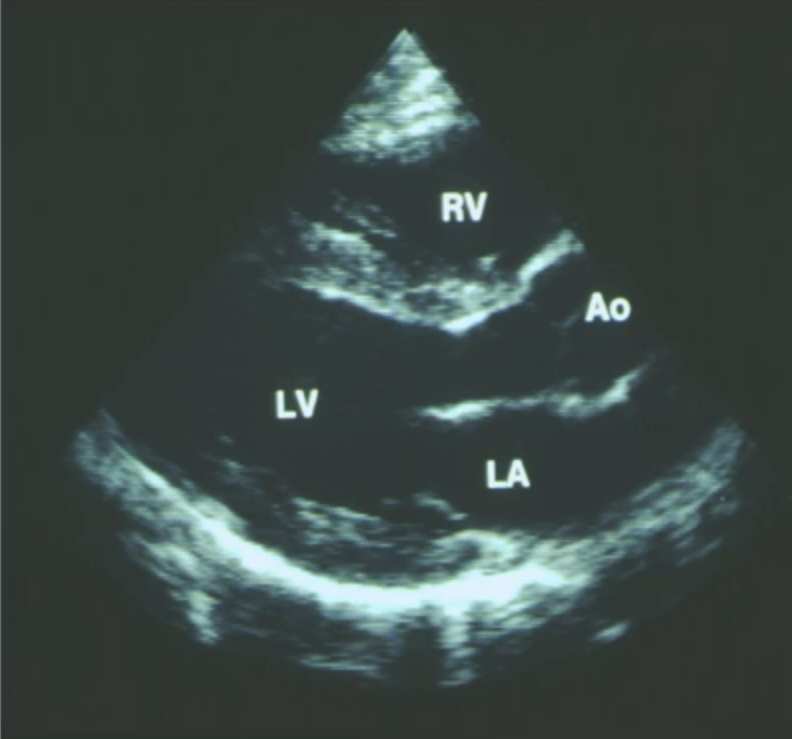

• Echocardiogram pt1:

• can also be used to see if valves are working correctly to ensure blood is pumped around the myocardium in the correct path

• this echocardiogram shows the mitral valve open, allow blood to flow from the left atrium to the left ventricle, representing diastole